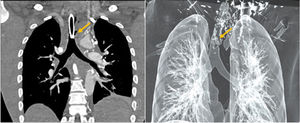

Varón, 26 años, con obstrucción de vía aérea superior por masa cervical anterior izquierda por linfoma B difuso de célula grande. Se inicia quimio- y radioterapia, a pesar de ello, presenta mala evolución, por lo que se realiza traqueotomía. Una semana después presenta nuevo episodio de obstrucción de vía aérea, objetivándose en videobroncoscopia (fig. 1) infiltración de la luz traqueal (asterisco azul) por la masa mediastínica (asterisco rojo), con cartílago traqueal prolapsado (flecha amarilla) y una fístula en la pared izquierda de 5 cm. La tráquea distal y la carina principal son normales. En tomografía (fig. 2A) se aprecia desestructuración de la tráquea (flecha amarilla), al igual que en la reconstrucción en 3D (fig. 2 B).